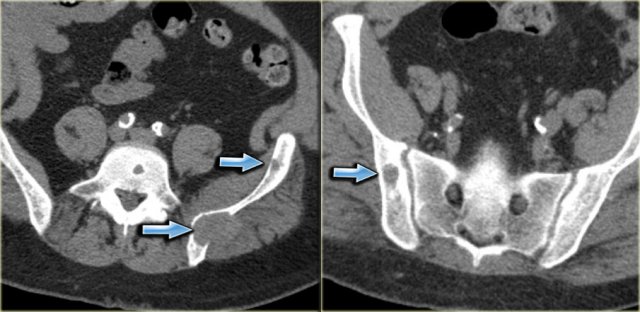

On the left a patient who had a nefrectomy for renal cell carcinoma and who was on dialysis.

Multiple well-defined osteolytic lesions were found on a follow up CT scan. The differential diagnosis included metastases and Brown tumors in hyperparathyroidism.

Biopsy revealed Brown tumor.